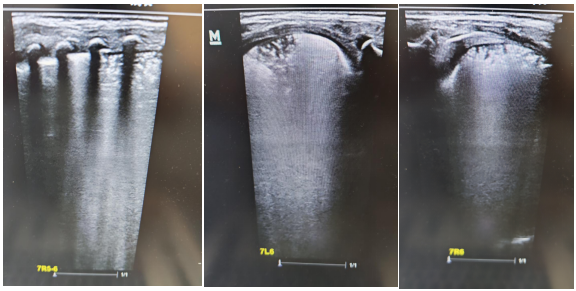

術(shù)前肺部超聲及CT均提示雙肺實(shí)變明顯